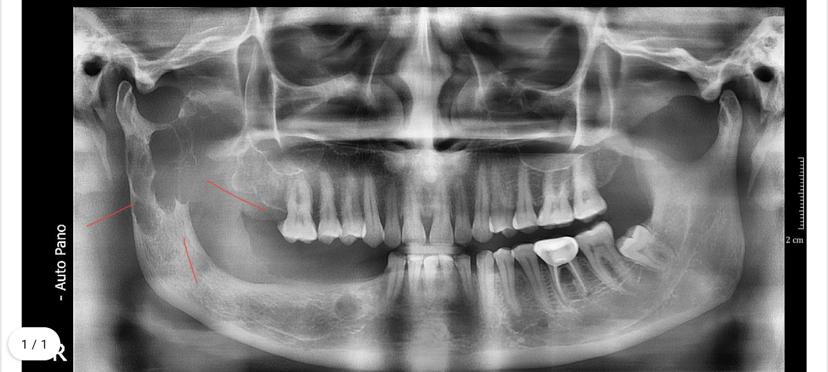

Condylar Fracture